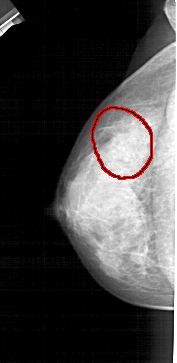

FILE: A_1446_1.LEFT_CC.OVERLAY

TOTAL_ABNORMALITIES 1

ABNORMALITY 1

LESION_TYPE CALCIFICATION TYPE AMORPHOUS DISTRIBUTION SEGMENTAL

ASSESSMENT 2

SUBTLETY 3

PATHOLOGY BENIGN

TOTAL_OUTLINES 1

BOUNDARY